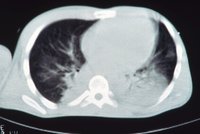

Je úžasnou mámou šesti dětí, poslední dvojčátka se přitom narodila před čtyřmi měsíci zcela nečekaně. Markéta (40) z Pardubicka procházela náročnou onkologickou léčbou, a že je těhotná, dlouho nevěděla ani ona, ani lékaři. Její zdravotní stav je nyní velmi vážný. Máma šesti dětí Markéta (40) bojuje o život: Dvojčátka přišla nečekaně!

Je úžasnou mámou šesti dětí, poslední dvojčátka se přitom narodila před čtyřmi měsíci zcela nečekaně. Markéta (40) z Pardubicka procházela náročnou onkologickou léčbou, a že je těhotná, dlouho nevěděla ani ona, ani lékaři. Její zdravotní stav je nyní velmi vážný. - Hlavní strana